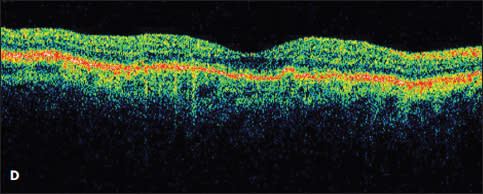

Figure 2. A new occult CNV with PED (A). After treatment with bevacizumab, OCT showed persistent subretinal fluid (B). The therapy was switched to ranibizumab, and after nine injections, the PED had slightly grown in size, but the subretinal fluid had resolved (C). Due to PED growth, the patient was switched to aflibercept, and after two injections, the subretinal fluid resolved, and the PED flattened (D).

Case 2. The second case involved a 99-year-old woman who presented with a new occult lesion in the left eye. There was loss of one line of vision at 20/40, and a new PED with associated subretinal fluid was noted on her OCT (Figure 2A). She was treated with three doses of monthly bevacizumab with a minimal response, and her vision declined to 20/50+2 (Figure 2B).

She was then switched to monthly ranibizumab. The subretinal fluid resolved with one injection, and her vision improved to 20/30. However, after nine injections of monthly ranibizumab, her vision declined to 20/40, with a small amount of intraretinal fluid and an enlarging PED (Figure 2C). This visit coincided with the commercially availability of aflibercept, and the treatment was changed to monthly 2.0 mg aflibercept. After two injections, her vision improved to 20/30, the PED flattened, and the subretinal fluid resolved (Figure 2D).